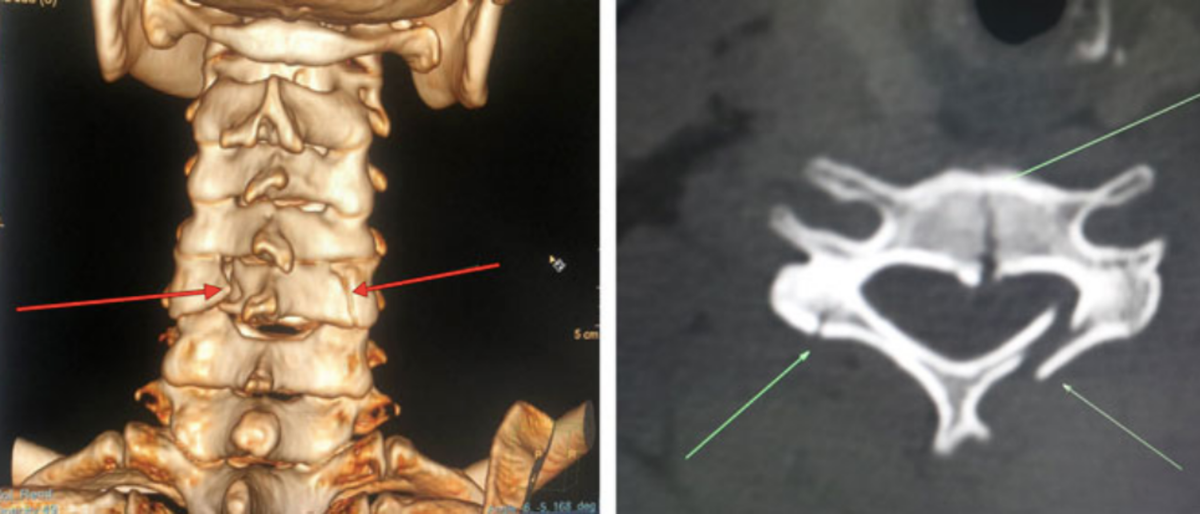

Trên hình ảnh chụp CT, cộng hưởng từ, cho kết quả vỡ thân đốt sống cổ đoạn C5 chèn ép gây hẹp ống sống, phù tủy. Người bệnh được chẩn đoán gãy đốt sống cổ đoạn C5, đụng dập tủy cổ ngang mức.

Tổn thương vỡ đốt sống cổ của nữ bệnh nhân (vị trí mũi tên chỉ). (Ảnh: BVCC )